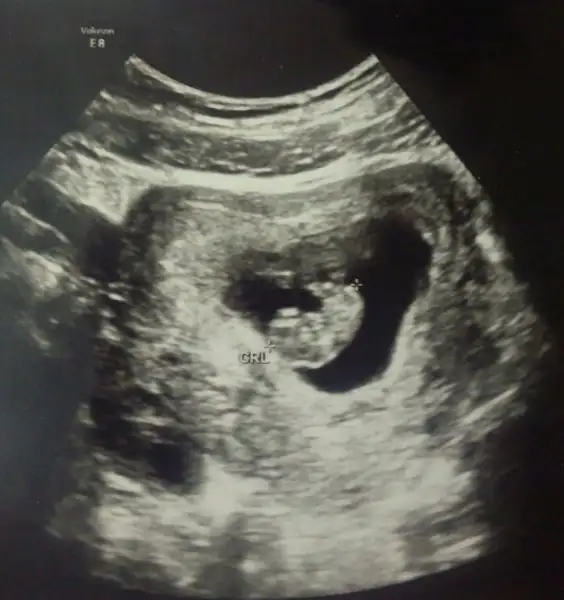

Ben şunu anlamadım ultrason kağıdını elime alınca bebegim bariz solda bu kesin.. Ama doktor ultrason u hep sagıma koyup bakıyor yani aslında bebek sağda ultrasonda direk bakınca da sağda.. Şimdi kağıda göremi yoksa ultrason a göremi yorum yapcaz

Canım benim ki 6+4 haftalikken bebek karından çekilen ultrasonda sağda duruyor şimdi bu kız mi erkek mi

İşte fark orda cnm karından Usg de öyle oluyor,vajinal da sağdaysa sağda soldaysa solda.usg kağıdın elindeyse yorum yapayım ben o yüzden usg karındansa veya vajinalsa diye yorum yapiyorum

Canim kağıdı elime alıp bakınca kese solda duruyor . Bu görüntü ters görüntü mu yani kağıda bakınca solda ama karında kese sağda mi oluyo